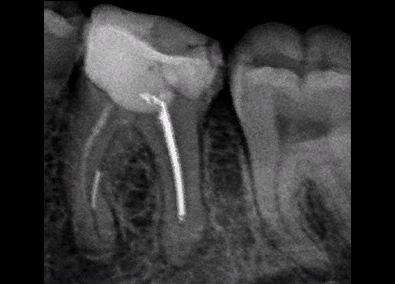

Лечение каналов зуба

Фото ДО

Фото ПОСЛЕ

Наведите для просмотра